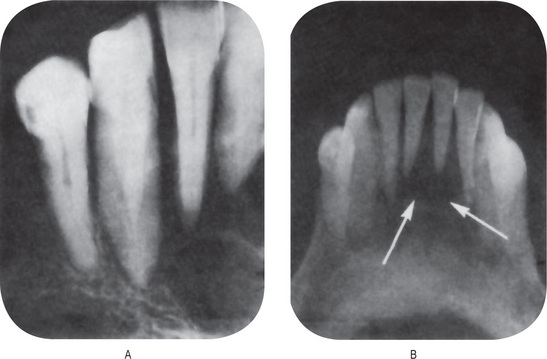

The teeth present a unique appearance characterized by the absence of cementum, presumably as a result of failure of cementogenesis, so that there is no sound functional attachment of the tooth to bone by periodontal ligament (Fig. 15-10). This lack of attachment is thought to account for the early spontaneous exfoliation of the deciduous teeth. Occasional foci of poorly formed cementum may be found on some teeth.

Figure 15-10 Hypophosphatasia.

A maxillary deciduous incisor of a patient with hypophosphatasia which was exfoliated at 15 months of age (A). The tooth root showed only a poor attempt at cementogenesis indicated by the granular, basophilic material between the dentin on the left and the periodontal fibers on the right (B) Courtesy of Dr Robert J Bruckner.